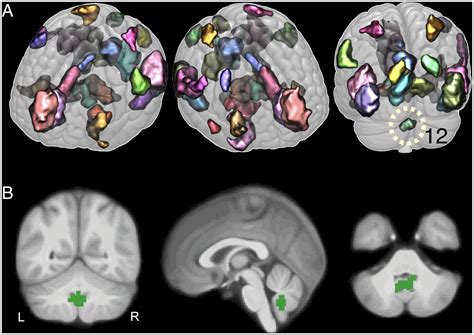

The University of Chicago Chronicle: Emotional memories stick when the brain works ‘in harmony,’ study finds

Many days blur together in our memories, but emotionally charged moments tend to leave a much sharper image. These experiences tend to stay with us for a long time, often becoming the milestones of ...